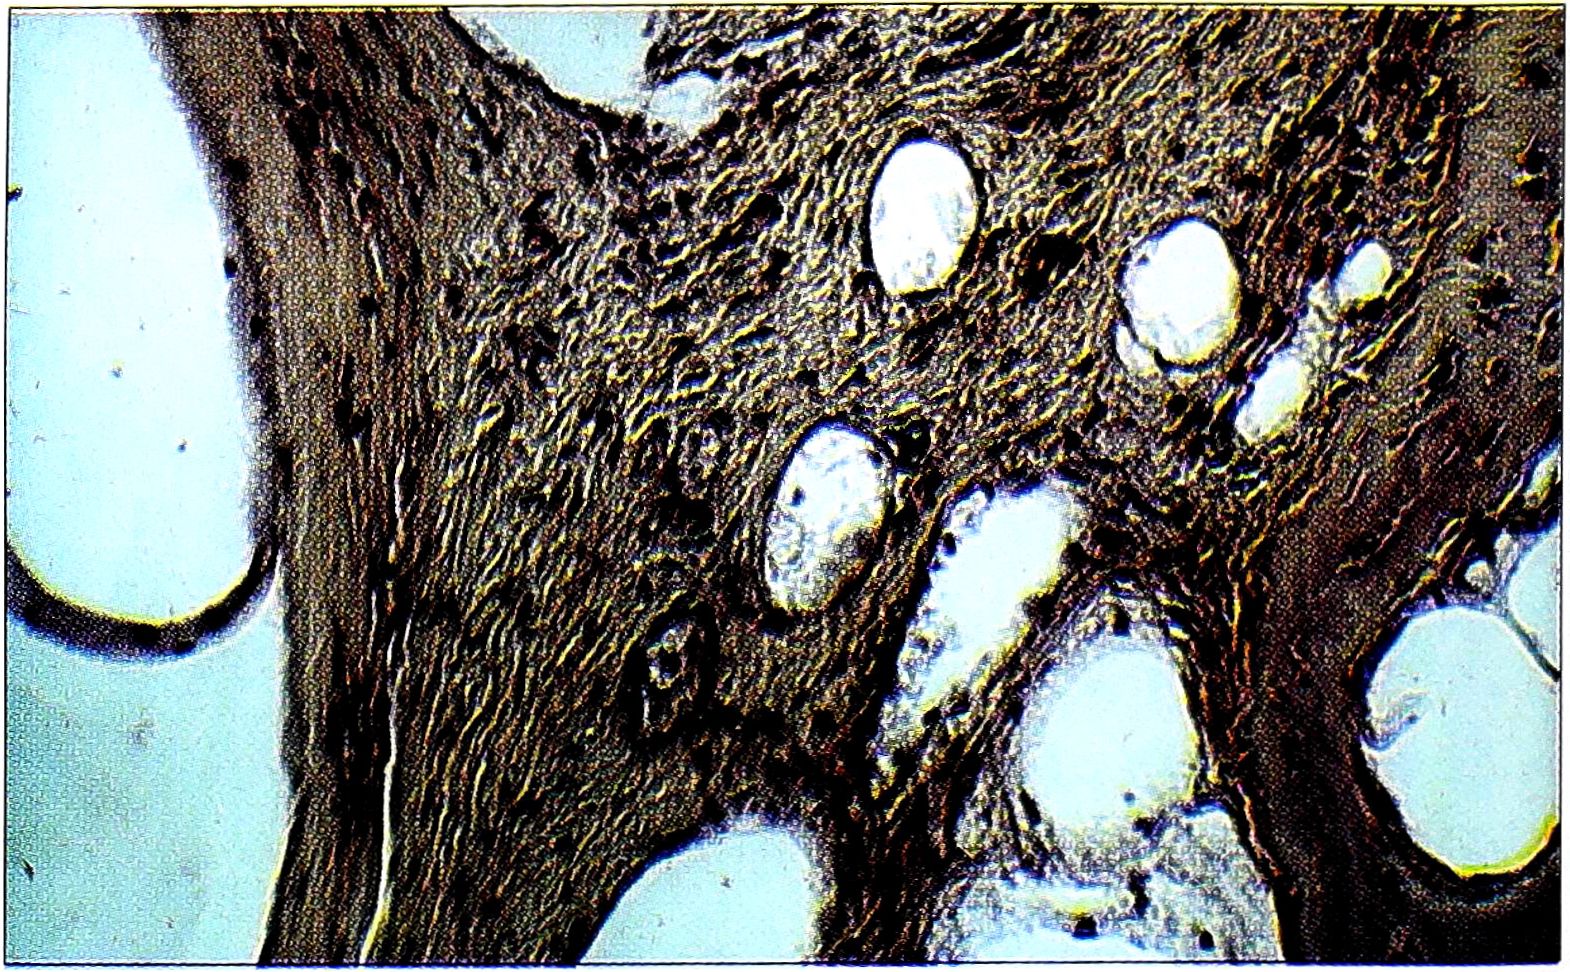

Истинные кисты (рис. 4) чаще располагались в субхондральной зоне, имели диаметр от 2-3 мм до 3 см, лишь в некоторых случаях в их просвете были видны элементы крови. Вблизи истинных кист обычно обнаруживались поля миксоматозной ткани, микрокровоизлияния, а также относительно многочисленные сосуды. В некоторых из этих резко расширенных сосудов наблюдались частичное исчезновение эндотелиальной выстилки и их запустевание, что, возможно, являлось отражением одного из возможных механизмов формирования истинных кист.

Рис. 4. Гистологическая картина при диспластическом коксартрозе с кистовидной перестройкой: вблизи истинной кисты располагаются резко расширенные сосуды, в некоторых из них отмечается исчезновение эндотелиальной выстилки (окраска гематоксилином и эозином, ув. 160).